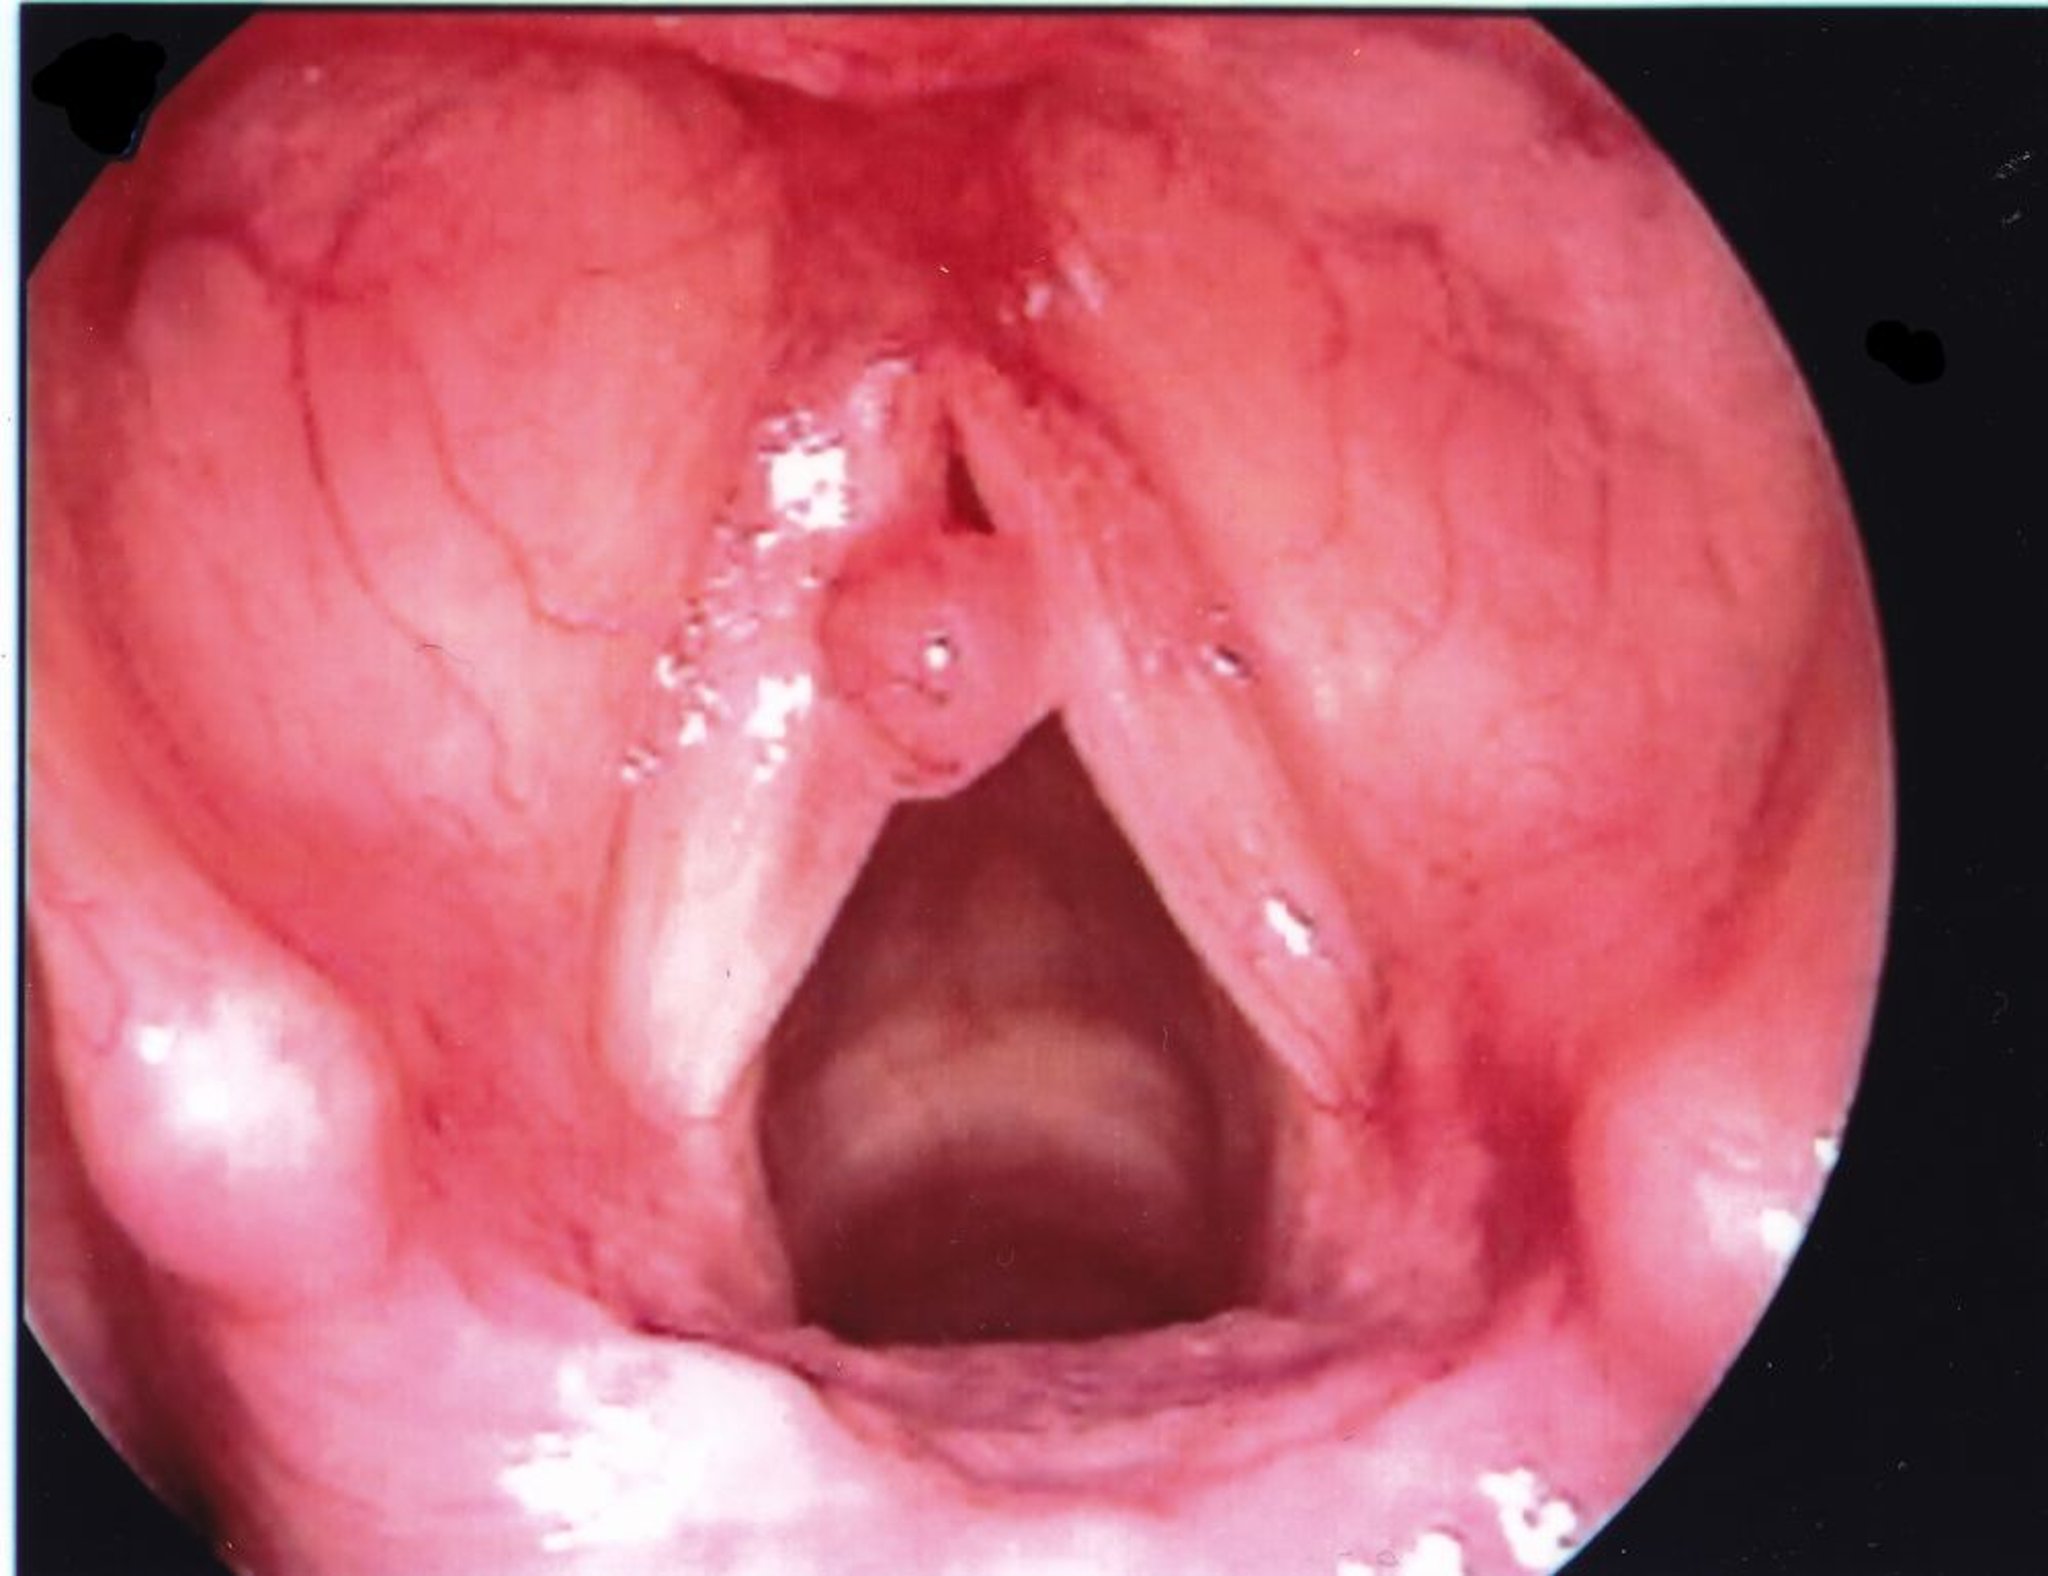

Polype des cordes vocales

Un polype de la corde vocale est habituellement unilatéral et est plus gros qu'un nodule.

Image fournie par Eiane Yanagisawa, MD.